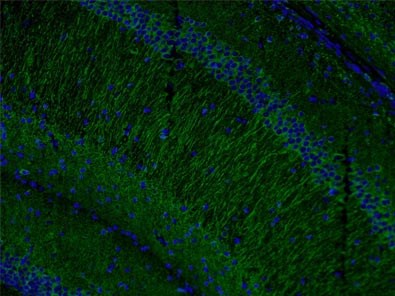

Also, levels of microtubule-associated protein 2 (MAP2, Figure 4) have been found to be reduced by the loss and gain of MeCP2 expression in accordance with the involvement of MeCP2 in shaping dendritic morphology.

Figure 4. Immunofluorescent analysis of (4% PFA) fixed mouse brain tissue using 17490-1-AP (MAP2 antibody) at a dilution of 1:50 and Alexa Fluor 488-conjugated AffiniPure Goat Anti-Rabbit IgG(H+L).